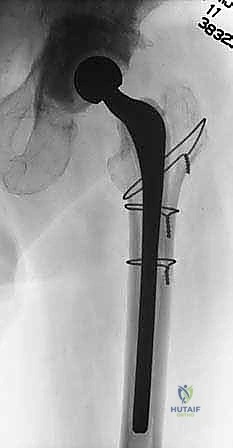

ماستر كلاس: جراحة استبدال مفصل الورك على مرحلتين لعلاج التهاب المفصل المزمن بعد الجراحة باستخدام فاصل محمل بالمضادات الحيوية

الماستر كلاس: التفاصيل الدقيقة لجراحة استبدال الورك على مرحلتين

هذا الإجراء ليس جراحة عادية؛ إنه "عملية إنقاذ" (Salvage Procedure) تتطلب أعلى مستويات المهارة، التخطيط ثلاثي الأبعاد، والخبرة الطويلة. الأستاذ الدكتور محمد هطيف يُجري هذه العمليات في صنعاء باستخدام أحدث بروتوكولات الأمان الجراحي.

المرحلة الأولى: الاستئصال، التنظيف الجذري، ووضع الفاصل

المرحلة الثانية: إعادة البناء وتركيب المفصل النهائي (Re-implantation)